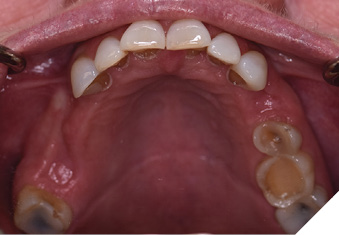

A 65-year-old woman comes to the office with the chief complaint of worn-down teeth, missing teeth, tooth sensitivity, especially on maxillary teeth and TMJ pain. Her past medical history was reviewed and was significant for asthma, insomnia, hypercholesterolemia, hypothyroidism, and anxiety disorder. She denied any sleep disturbances. Her medications included salbutamol, ezetimibe, quetiapine, and levothyroxine. She referred to being allergic to dust and shellfish and sensitive to propofol. She had a right mastectomy in 2014 due to breast cancer. No chemotherapy or radiation was done. Her diet was considered normal, and she denied any consumption of acidic drinks and denied any history of regurgitation. She denied any parafunctional habits during the day. She was using a maxillary transitional partial denture since she had lost some of her teeth due to fracture and caries. No other problems were evidenced. Intraoral exam showed moderate attrition lesions of posterior teeth, porcelain fused to metal crowns on teeth 46 and 47 had the porcelain portion worn down, exposing the metal substructure. Missing teeth included teeth 14,15,16,18,24,28, 36,38,48. Palatal surfaces of maxillary anterior teeth also appeared worn down. An abfraction lesion was found on tooth 23. No carious lesions were found in any of her teeth. Composite restorations on mandibular anterior teeth were chipped or were missing (Figs. 6-11) She also presented with limited mouth opening: 35 mm interincisal distance at maximum opening. There was bilateral pain on palpation of preauricular areas. Her pain was the worst early in the morning which suggested night parafunction. No crepitus, or joint clicking were found.

Fig. 6

Fig. 7

Fig. 8

Fig. 9

Fig. 10

Fig. 11